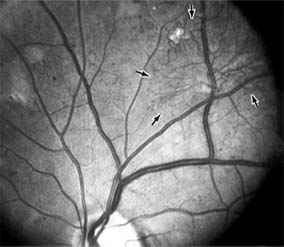

The visual and electrophysiologic dysfunctions associated with diabetes probably result from the local vascular abnormalities and the systemic metabolic effects of the disease to which the retina is subjected. A characteristic blue-yellow color vision abnormality develops, and hue discrimination may be impaired. Contrast sensitivity may be reduced in patients, even in the presence of normal visual acuity. Visual field testing may show relative scotomas corresponding to areas of retinal edema and nonperfusion, and abnormalities in dark adaptation have also been described. Electroretinographic abnormalities bear a relationship to the severity of retinopathy and may aid in predicting progression of retinopathy. Fluorescein angiography is invaluable in defining the microvascular abnormalities of diabetic retinopathy (Figures 10-21 and 10-22). Large filling defects of capillary beds-"capillary nonperfusion"-show the extent of retinal ischemia (Figure 10-23) and are usually most prominent in the midperiphery. The fluorescein leakage associated with retinal edema may assume the petaloid configuration of cystoid macular edema or may be diffuse. Other fluorescein abnormalities include vascular loops and intraretinal shunts. The focus of treatment in patients with nonproliferative diabetic retinopathy and no macular edema is treatment of hyperglycemia and intercurrent systemic disease. A controlled clinical trial has shown that aldose reductase inhibitor therapy does not prevent progression of diabetic retinopathy. Focal argon laser treatment of discrete points of retinal leakage in patients with clinically significant macular edema, principally defined as thickening of the retina at or within 500 0x0003bcm of the center of the macula, reduces the risk of visual loss and increases the likelihood of visual improvement (see Chapter 24). Eyes with diabetic macular edema that is not clinically significant should usually be monitored closely without laser treatment. Since macular edema may be present with little or no change in visual acuity and requires slitlamp biomicroscopic retinal examination for full evaluation, primary health care providers should recognize the importance of prompt and early referral of diabetic patients to the ophthalmologist.

Figure 10-21

Figure 10-21: Fluorescein angiogram in nonproliferative diabetic retinopathy shows microaneurysms (arrow) and perifoveal retinal vascular changes.

Figure 10-22

Figure 10-22: Late phase fluorescein angiogram shows hyperfluorescence typical of noncystoid diabetic macular edema.